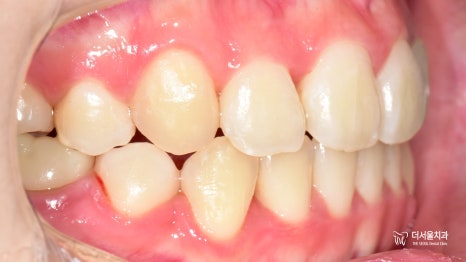

구내 사진을 보면

삐뚤빼뚤 했던 치열들이

제 위치를 찾아가 있는 모습입니다.

정중선도 잘 맞고

이전에 크라운을 올려드렸던

22번도 잘 어우러지고 있네요.

스마일라인 또한 자연스럽고

예쁘게 개선되었습니다!